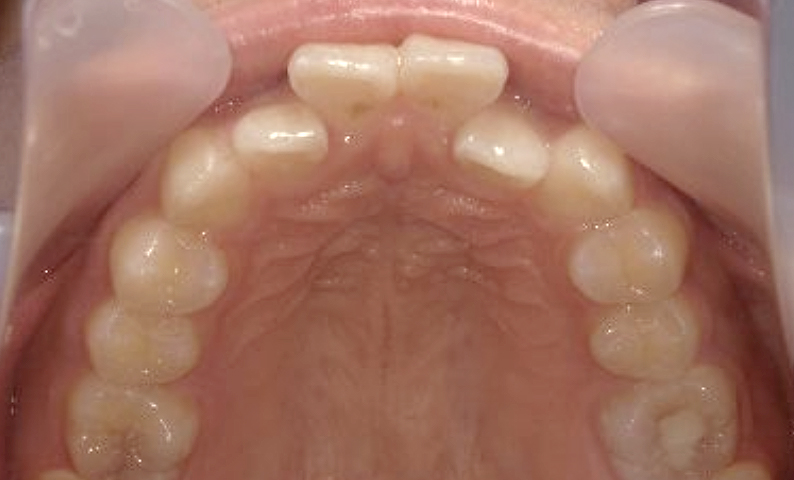

症例_025 上顎だけの部分矯正

治療期間:7ヶ月金額:30万円+税女性前歯のガタガタ上の前歯だけ

| Before | After |